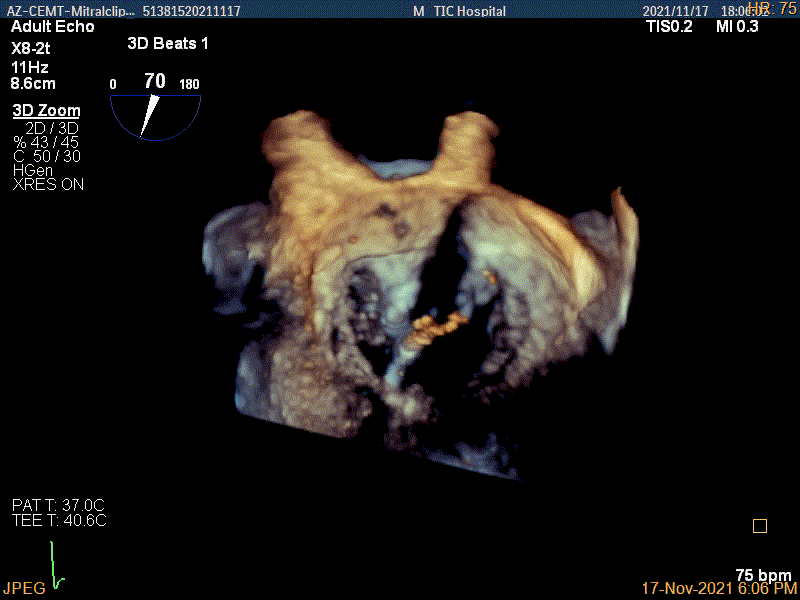

3D视图两个夹子近似并排排列

3D-color视图下两个夹子间少量残余反流

3、手术实操:充分考虑患者病情后决定实施第二种预案,NTR的小夹子尽可能贴近前交界区,夹合脱垂组织,反复调整后完成第一步操作,夹合了脱垂组织和前叶,幸运的是此时评估残余反流微少量;但是放开第一个夹子后,A1-P1反流量增加,为了进一步稳定第一个夹子和减少反流,决定实施第二步,在A1-P1区实行进一步夹合置入XTR。术后评估反流明显好转,两个夹子稳定。